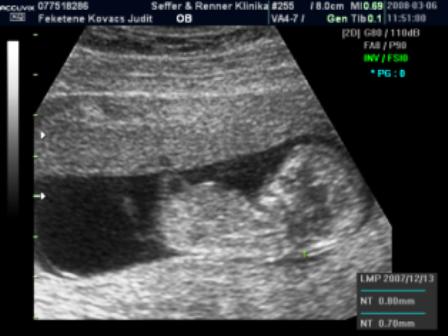

Mi holnap este megyünk.Ilyenkor még végigjárjuk a nagyszülőket + egy kis vásárolgatás, este 9-től hamarabb nem hiszem, hogy hazaérünk, de jövök majd a beszámolóval és a fotóval.